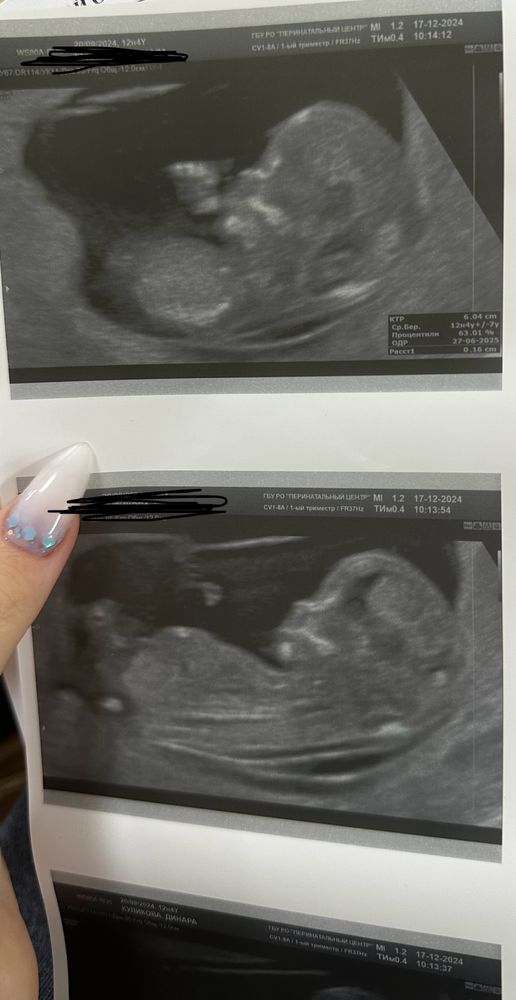

Детёныша с пальцем во рту видим 🤣👍 Классная фотка!

Но по этим фото не определить пол, к сожалению(

Жанна, ну вот я тоже думаю что не определить , а врач там уже на определяла 😂 с пальца во рту сама смеялась , он там и привет махал прям в кадр и кулак показывал 😂

Динара Куликова, не, в реальном времени все хорошо видно:) Мне обоих детей в 12 недель уже говорили на хороших аппаратах) просто именно по этим фото не понять. Бугорка не видно, ракурс не тот.

На первой фотке уже палец во рту 😂

Кажется мальчик, половой бугорок под углом относительно спинке. Но фото не очень качественное, могу и ошибаться